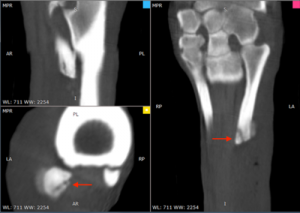

The Equina® is a multi-slice, fan beam helical CT and as such, provides superior images when compared to radiographs and cone-beam CT imaging devices. Imaging is extremely fast (more on this later), so motion artifacts like those created by cone-beam CTs are not produced. In addition, cone-beam CTs require operators to rescan using separate algorithms for soft tissue, while Equina® can simply post-process the images for greater detail. For clinicians, this unmatched accuracy means superior diagnoses across more pathologies of the head, neck, and limbs, as well as more customized treatment plans for complex syndromes, including dental tumors and navicular disease.